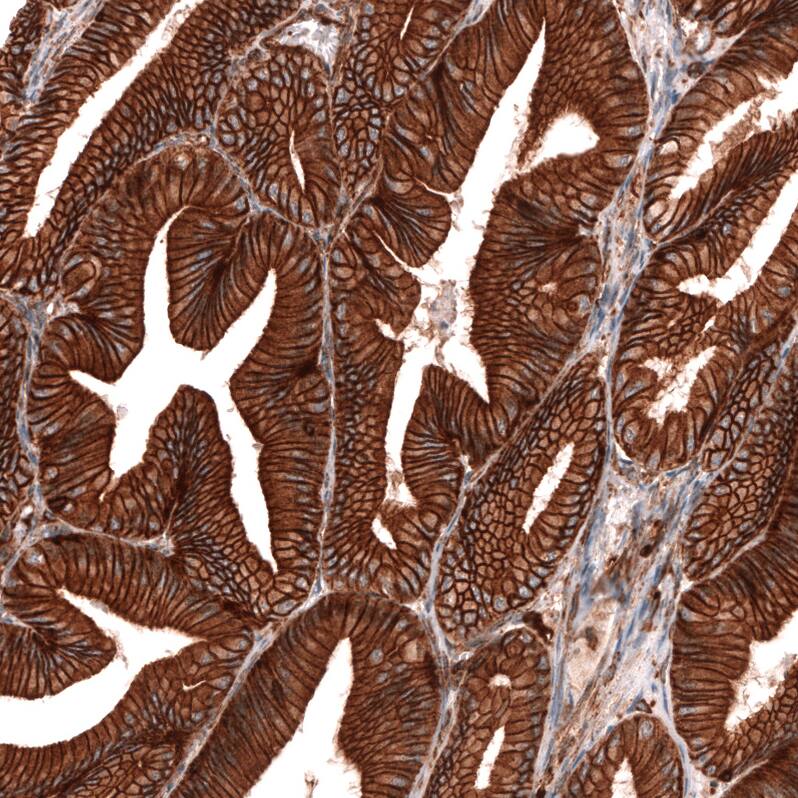

Staining of human pancreas shows strong membranous positivity in exocrine glandular cells.